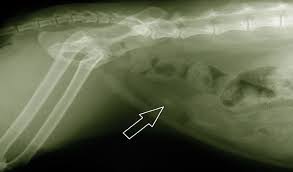

1 Little 2 Little 7 Little Bladder Stones Cat Care Clinic

1 Little 2 Little 7 Little Bladder Stones Cat Care Clinic from i0.wp.com

They include changes in diet or water intake, underlying metabolic disease, congenital problems, and bacterial infections of the urinary tract. How can u get rid of calcium stones? The scientific term for the development of stones in ay part of the urinary tract is urolithiasis.some breeds are predisposed to the condition, including persian, himalayan and burmese cats.male cats are also more likely to develop problematic kidney stones due to having a narrower ureter, especially those which have been neutered. What are the clinical signs of oxalate bladder stones? The compounds in the cat's diet will depend on the composition of the bladder stones. This diet increases urine volume to decrease struvite and calcium oxalate levels, and also dissolves struvite bladder stones. Other cats with crystals or bladder stones may have blood in their urine and may urinate frequently, passing only small quantities of urine each time. These diets are typically lower in magnesium and phosphorus, and are designed to keep the urine ph neutral.